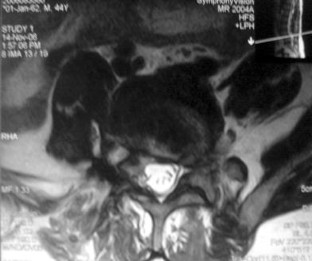

We report a case of L4–L5 traumatic anterolisthesis. The patient was treated surgically 4 months after the injury. His radiological and operative findings showed L4 inferior facet tip fracture, L4–L5 anterior displacement and left L4–L5 foraminal disc protrusion. Decompression, reduction with L3, L4, L5 pedicular screw fixation, L4–L5 disc excision and interbody cage insertion with autologous bone grafts were done. Flexion type injury was thought to be the probable mechanism.

Fig. 3